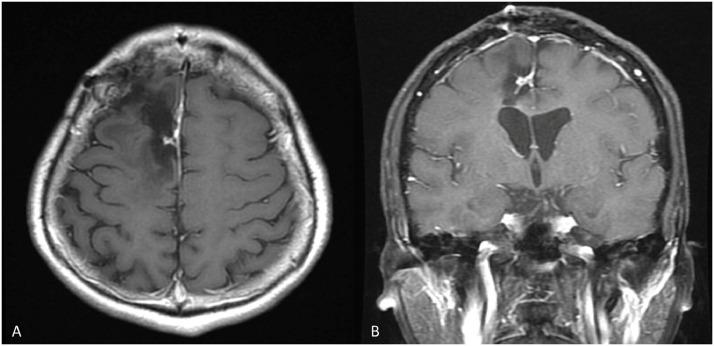

Hemangioblastomas are rare and benign tumors of the central nervous system. They account for 1.5%-2.5% of all intracranial tumors and have an incidence of 3.2%. The resemblance of hemangioblastomas to other tumors renders preoperative diagnosis and management challenging. Herein, we report a case of a supratentorial hemangioblastoma accompanied by extensive reactive gliosis and diagnosed through magnetic resonance imaging. In addition, we review the relevant literature.